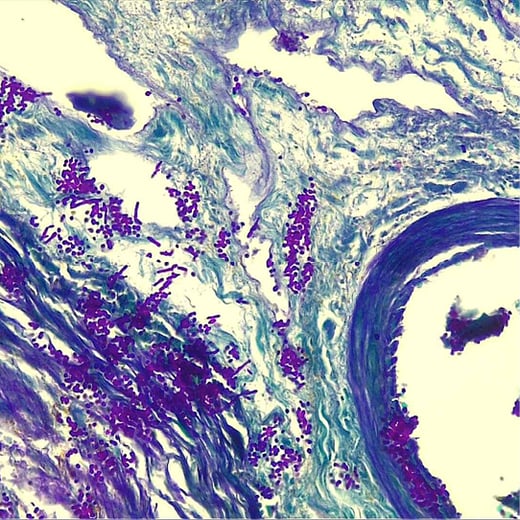

Ethos Biosciences image of Gomori Trichrome Stain

Gomori Trichrome Stain

The Gomori Trichrome method provided a shorter staining process to Masson’s Trichrome method, yielding similar results. The Gomori Trichrome demonstrates the collagen fibers in a brilliant green shade. This color option is unique to the Gomori Trichrome method.